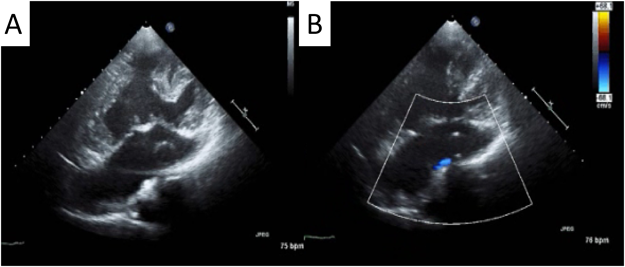

術翌日に一酸化窒素吸入終了の上,人工呼吸器から離脱した.抜管後の動脈圧は110/56 mmHg,平均肺動脈圧は10 mmHg,酸素投与下にSpO2は96%であった.経口摂取開始し,抗凝固療法を開始した.術後3日目にICU退室した.術後15日目に胸腔ドレーン抜去.術後32日目に退院した.胸部X線上,CTRは術前71%から術後は61%に改善した.退院前の造影CTではグラフト圧迫などの所見は認めなかった(Fig. 6).

Pediatric Cardiology and Cardiac Surgery 33(3): 249-255 (2017)

Fig. 6 Postoperative computed tomography (CT)

(A) Postoperative CT images. (B) The diameter of the inferior vena cava had decreased. (C) Coronal image showing a central pulmonary artery graft and the intraatrial conduit.

退院時のSpO2は93%であった.採血上,AST値は26 IU/L,AST値は22 IU/L,TBは1.1 mg/dLと正常化した.術後3ヶ月で職場に復帰し,術後3ヶ月でBNP値は正常化した.術後1年が経過したが,心臓超音波検査上は,房室弁逆流はほとんど認めていない(Fig. 7).術後2年の経過で発作性上室性頻脈の再発は認めていない.

Fig. 7 Postoperative transthoracic echocardiography

(A) The intraatrial conduit was observed. (B) Fenestration flow and the disappearance of common atrioventricular valve regurgitation were evident.